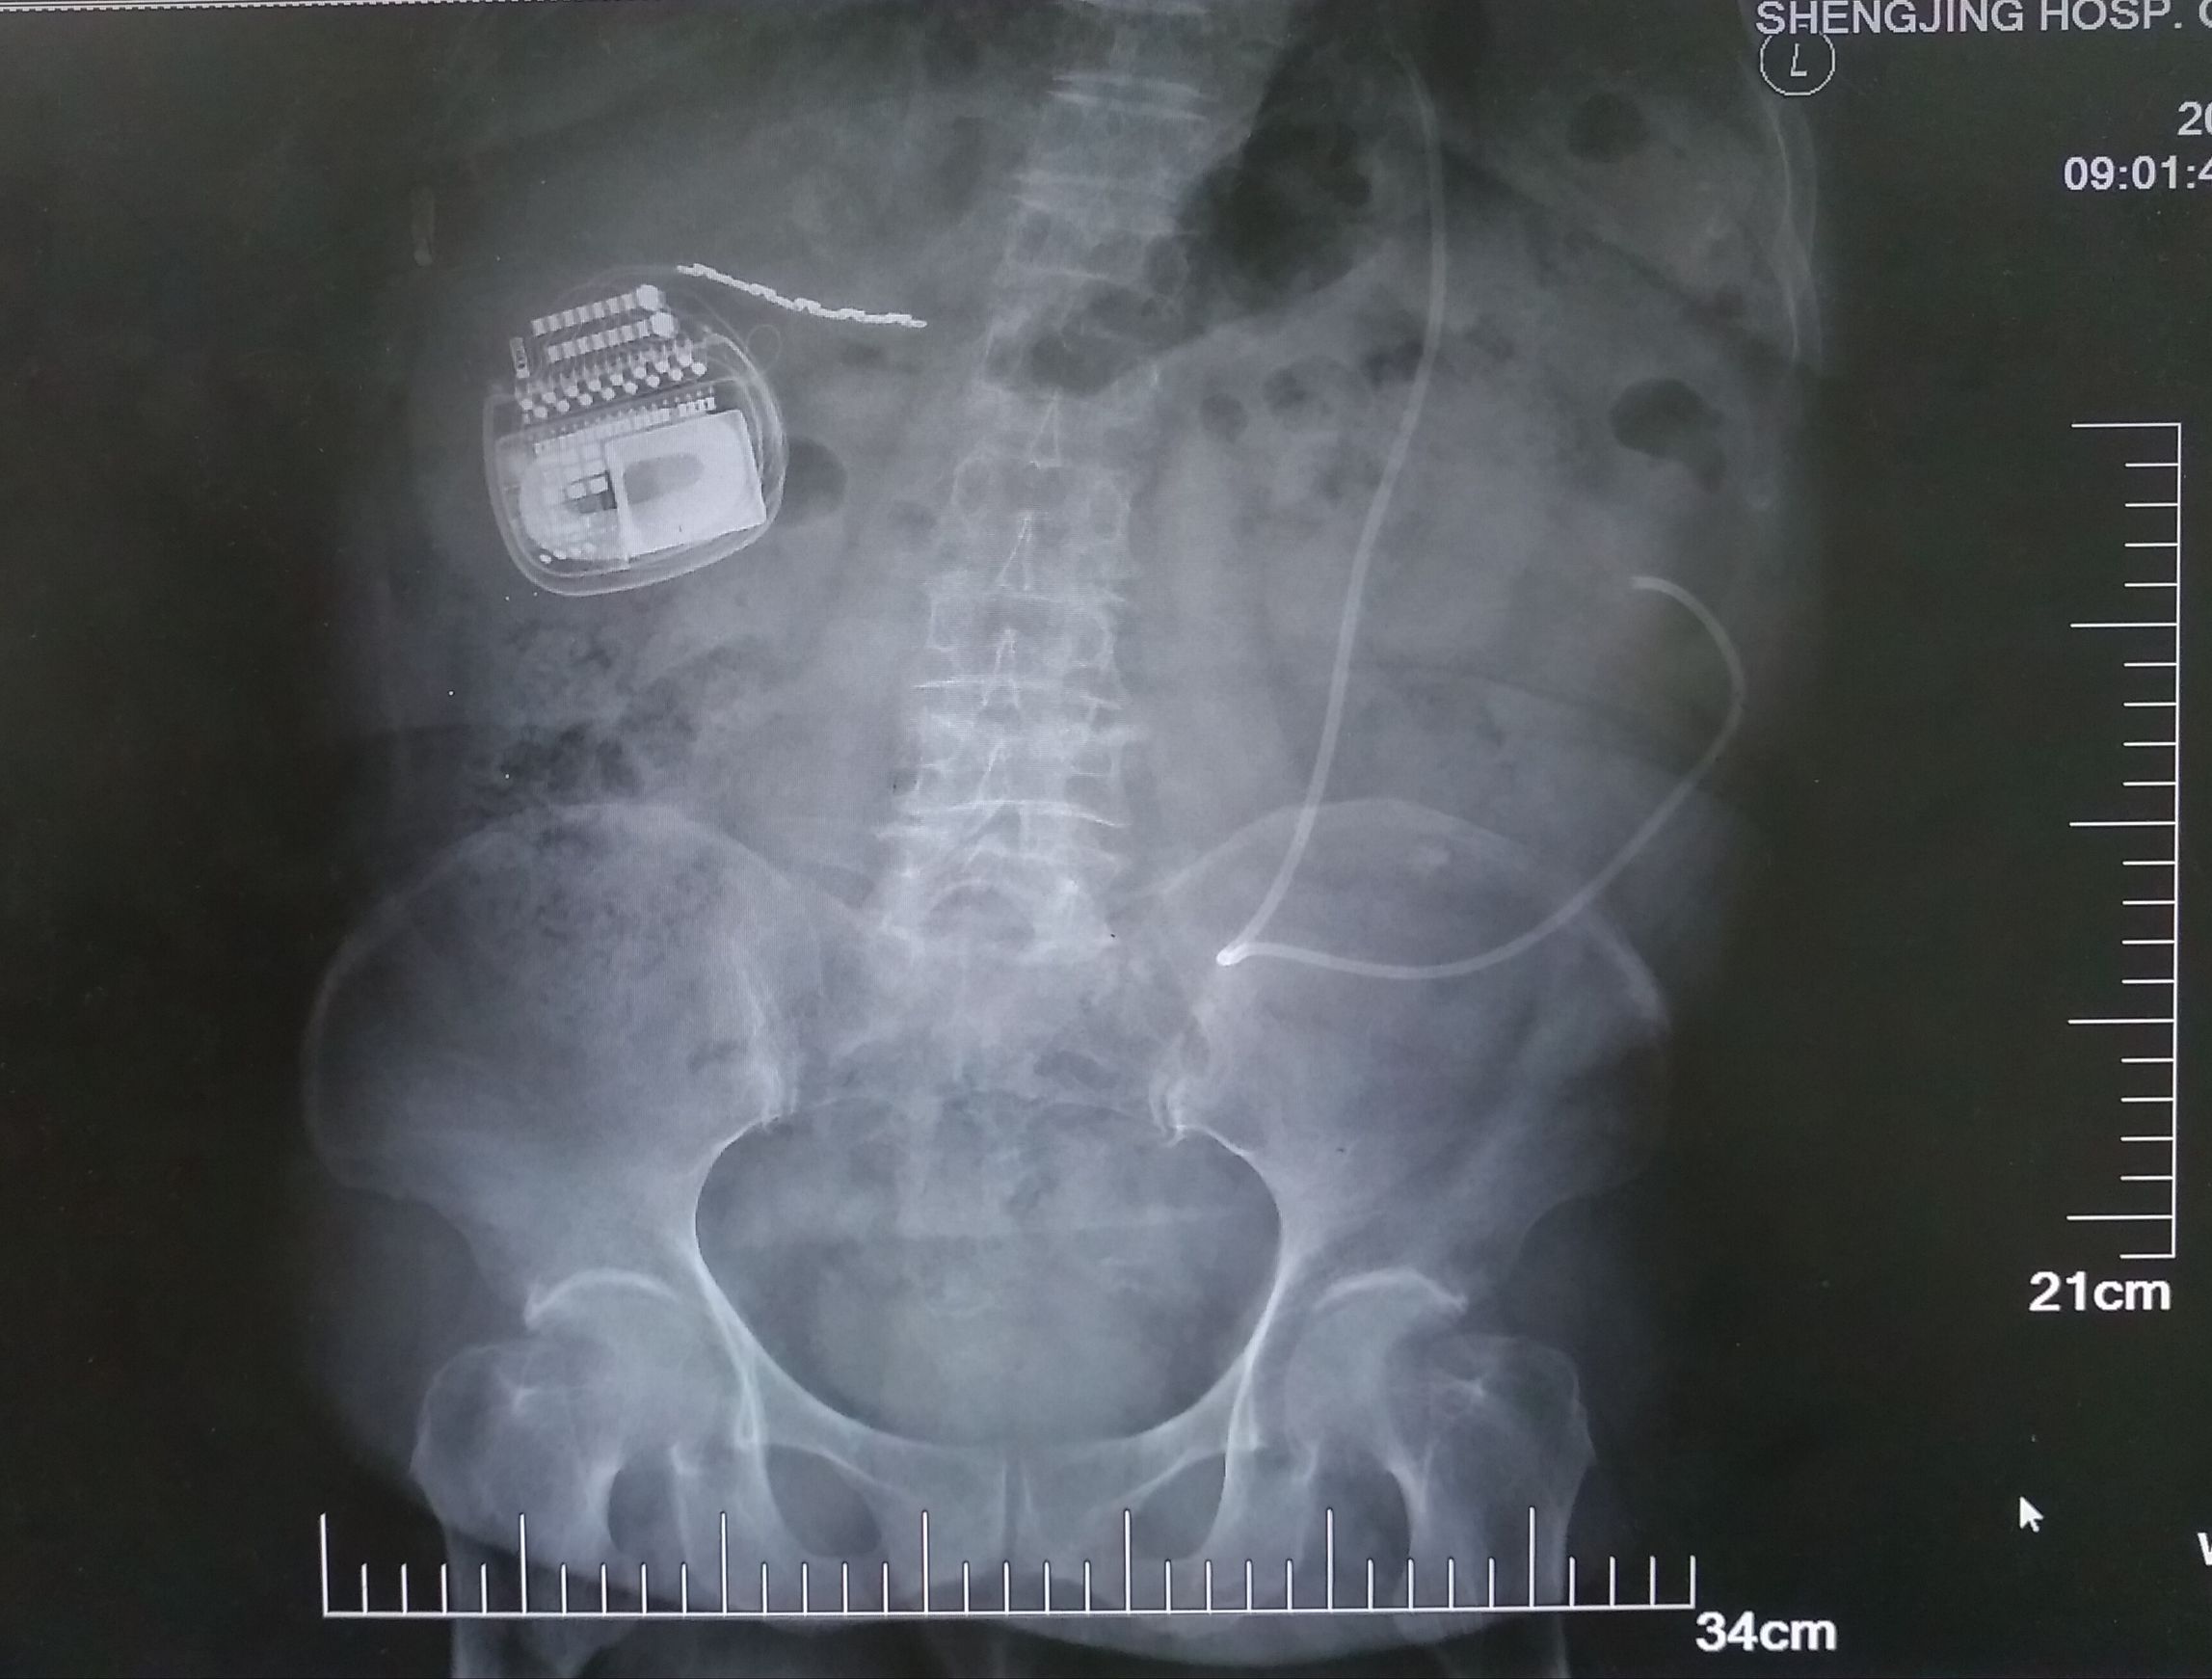

首先,鲍民副主任为高女士做了一期电极植入手术,在疼痛区域中心植入了一枚宽大的外科电极。手术过后,体内的电极通过延长导线和体外的临时刺激器连接上了。在开机的那一刹那,困扰高女士好几年的疼痛一下子就止住了。再也没有疼痛的袭扰,取代的是一丝丝电流的酥麻感,疲惫的高女士很快就进入了梦乡。 经过了七天的观察,在确认疗效满意后,鲍民副主任为高女士行二期手术,植入了最新的可充电式、可感知体位变化的Restore Sensor®刺激器(图)。术后高女士疼痛缓解,可平卧,睡眠质量得到很大改善。

图 二期植入可充电刺激器及电极位置